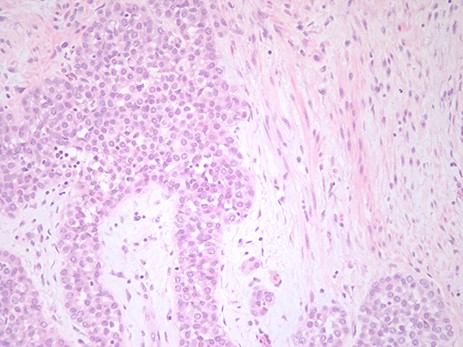

The pathological figure demonstrates LCIS in the background of a fibroadenoma. The image is at ×20 with an H&E stain.

Final pathology demonstrated LCIS entirely confined to a large fibroadenoma (Fig 1). The mass measured 3.5 × 2.5 × 2.0 cm. There was no evidence of LCIS in the breast tissue surrounding the fibroadenoma.